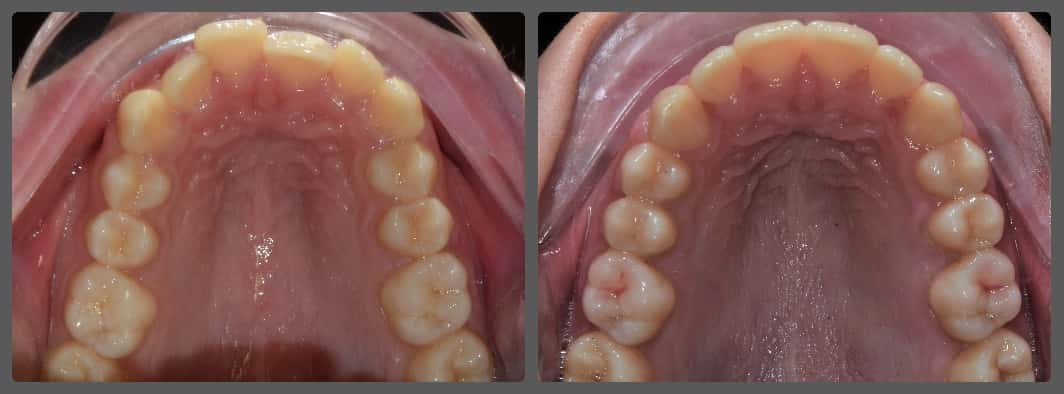

Balázs súlyos alsó torlódása miatt keresett fel magánrendelésemen. A diagnosztikus vizsgálatok során előbbin túl alsó-felső fogívszűkületet, valamint nyitott harapási hajlamot állapítottam meg. Kezelését Pitts21 alsó-felső rögzített fogszabályozó készülékkel kezdtük meg. A nyitott harapási hajlamot a hátsó fogakra helyezett harapásemelővel kontrolláltuk. A torlódott fogaknak tolórugóval és interproximális redukcióval teremtettünk helyet, és intermaxilláris gumihúzással tökéletesítettük a harapást. A fogszabályzó kezelés teljes időtartama alatt Balázs 110%-osan együttműködő volt, ezért 21 hónap alatt sikerült kiemelkedő végeredményt elérnünk.